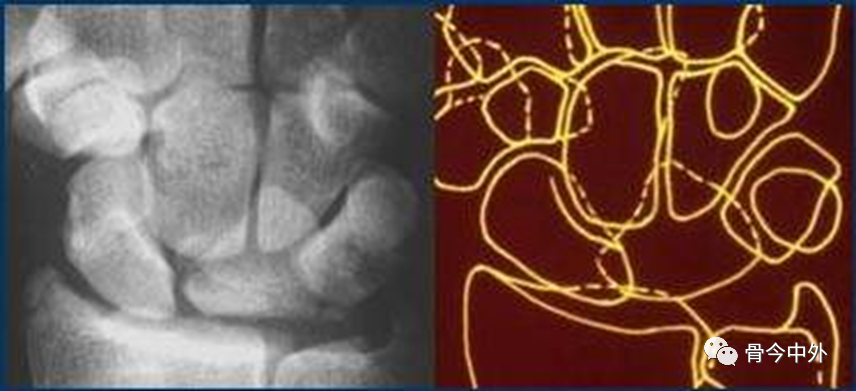

图17

腕骨弧线中断;弧线中断提示骨折或韧带断裂导致的半脱位或脱位。上图显示弧线Ⅰ在月骨-三角骨关节处的中断。